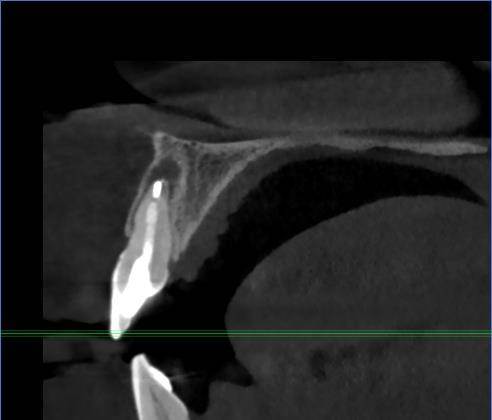

И есть второй зуб с проблемой около корней -16 (РФ зуб). Перед брекетами уже перелечивали корни в 2016 году.

Сейчас опять говорят надо заново перелечивать перед протезированием.

Имеет ли смысл? (а то так до бесконечности можно перелечивать и дешевле удалить было и имплантант поставить).16.jpg.c48b680915f979a9e4778f4248ff39c7.jpg16-1.jpg.c116f77ce054f4d184897797128c176a.jpg16-2.jpg.675bd02ec47e5582670209e0dc324a7f.jpg16-3.jpg.ece96fa59fc264e0e38c691000fc9780.jpg16-4.jpg.a269497c8968ad8cbd4d3c558c480d90.jpg16-5.jpg.e4f929dd96c9da3ce934b217da02a634.jpg16-6.jpg.260d3caac245b47f76f4f53ca38317c4.jpg